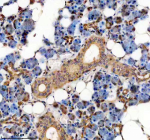

IHC analysis of TMED10 using anti-TMED10 antibody. TMED10 was detected in a paraffin-embedded section of human thyroid cancer tissue. Heat mediated antigen retrieval was performed in EDTA buffer (pH 8.0, epitope retrieval solution). The tissue section was blocked with 10% goat serum. The tissue section was then incubated with 2 ug/ml rabbit anti-TMED10 antibody overnight at 4oC. Peroxidase Conjugated Goat Anti-rabbit IgG was used as secondary antibody and incubated for 30 minutes at 37oC. The tissue section was developed using an HRP secondary and DAB substrate.